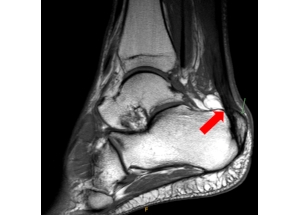

Most patients present with heel pain which can be associated with limping or swelling. The pain is most prominent while walking or other weight-bearing activities. On examination of the heel, a bump can often be appreciated as seen below. Signs of inflammation such as swelling, warmth, redness, and tenderness over the heel may also be present. An XRAY may demonstrate a bony prominence of calcaneus, as well as associated bone spurs at the Achilles tendon insertion. An MRI can demonstrate bony bodies adjacent to the calcaneal insertion of the Achilles tendon and can also evaluate for any underlying Achilles tendinopathy.